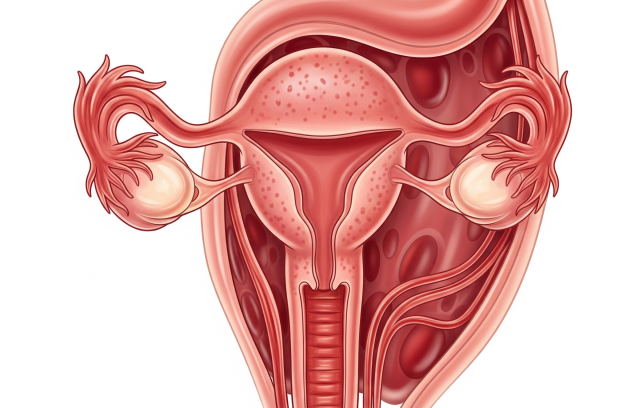

بطانة الرحم المهاجرة: كيف تؤثر على الخصوبة وفرص الحمل؟

بطانة الرحم المهاجرة أو ما يُعرف طبيًا بـEndometriosis، هي من أكثر الحالات النسائية شيوعًا وتعقيدًا، خاصةً حين ترتبط…

كل ما تريد معرفته عن الحمل الطبيعي بالتفصيل وكيفية حدوثه

الحمل الطبيعي بعد الزواج مباشرًة، يسعى كثير من المتزوجين إلى الحصول على حمل طبيعي بأسرع وقت ممكن، ولكن…

تأخر الحمل هو عدم حدوثه بعد مرور عام من الزواج، وذلك يعود لأسباب مختلفة قد تكون لدى الرجل…